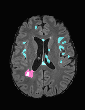

In recent years, data-driven machine learning (ML) methods have revolutionized the computer vision community by providing novel efficient solutions to many unsolved (medical) image analysis problems. However, due to the increasing privacy concerns and data fragmentation on many different sites, existing medical data are not fully utilized, thus limiting the potential of ML. Federated learning (FL) enables multiple parties to collaboratively train a ML model without exchanging local data. However, data heterogeneity (non-IID) among the distributed clients is yet a challenge. To this end, we propose a novel federated method, denoted Federated Disentanglement (FedDis), to disentangle the parameter space into shape and appearance, and only share the shape parameter with the clients. FedDis is based on the assumption that the anatomical structure in brain MRI images is similar across multiple institutions, and sharing the shape knowledge would be beneficial in anomaly detection. In this paper, we leverage healthy brain scans of 623 subjects from multiple sites with real data (OASIS, ADNI) in a privacy-preserving fashion to learn a model of normal anatomy, that allows to segment abnormal structures. We demonstrate a superior performance of FedDis on real pathological databases containing 109 subjects; two publicly available MS Lesions (MSLUB, MSISBI), and an in-house database with MS and Glioblastoma (MSI and GBI). FedDis achieved an average dice performance of 0.38, outperforming the state-of-the-art (SOTA) auto-encoder by 42% and the SOTA federated method by 11%. Further, we illustrate that FedDis learns a shape embedding that is orthogonal to the appearance and consistent under different intensity augmentations.